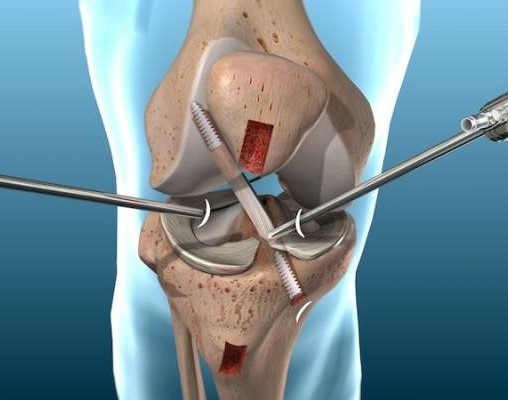

Dr. Shubham Thori With expertise in advanced orthopedic care, like treating bone, joint, and Pain with precision and compassion. From diagnosis to recovery, the focus is on restoring mobility, reducing pain, and helping patients get back to an active, healthier life, with the help of his experience in recognized Hospital MYH (Maharaja Yashwant Rao Hospital, Indore)

Our Expertise

What We’re Offering